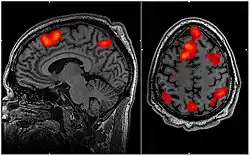

In the image on the right: "Working memory tasks typically show activation in the bilateral and superior frontal cortex as well as in parts of the superior bilateral parietal cortex. The highlighted regions showed significantly different activation between an individual performing a 1-Back task versus a 2-Back task."[11]